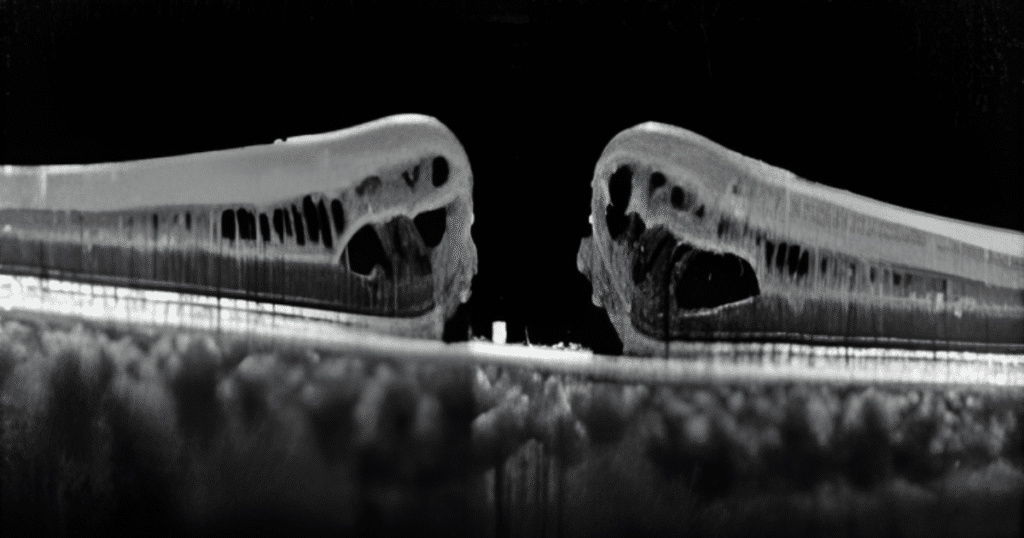

1. OCT (Tomografia de Coerência Óptica)

É o padrão ouro. A tecnologia cria cortes tridimensionais da mácula, revelando:

- Formato do buraco

- Diâmetro

- Presença de tração

- Estágios do dano

É como uma “ressonância magnética da retina”, permitindo ver detalhes em micrômetros.